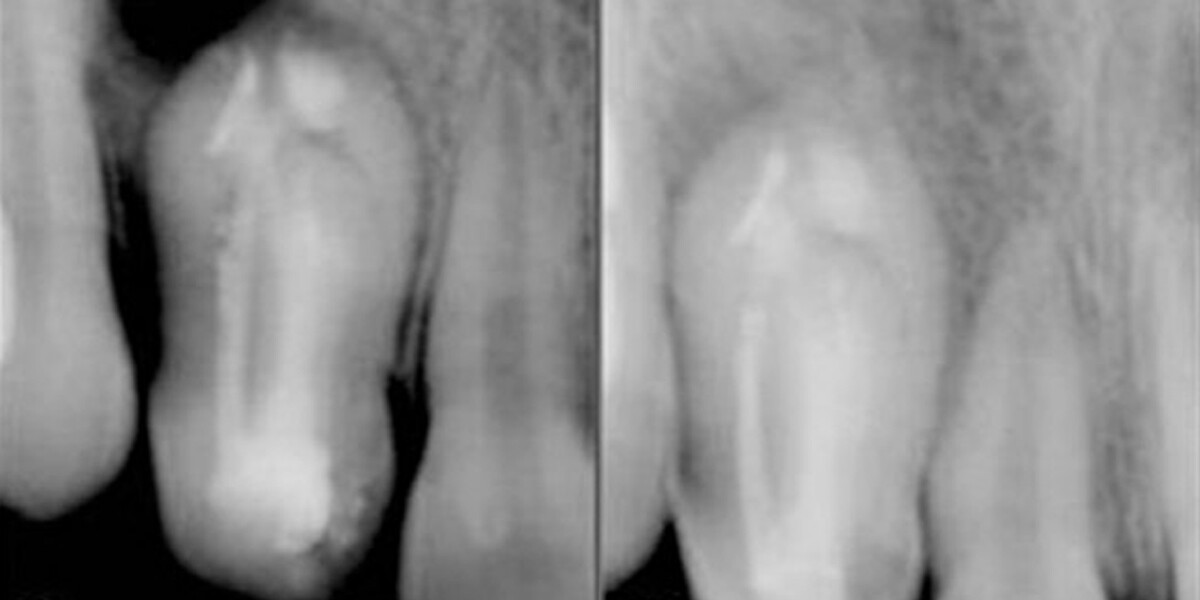

13-летняя девочка была направлена в Департамент детской и превентивной стоматологии в Rural Dental College и Hospital в Лони, Индия, с главной жалобой на недавно возникшую припухлость во фронтальном отделе верхней челюсти справа. Пациентка описала диффузное опухание в области щеки справа спереди, которое привело к поднятию крыла носа. При интраоральном осмотре в боковом резце верхней челюсти было обнаружено углубление, наблюдался незначительный дисколорит коронки, зуб положительно реагировал на вертикальную перкуссию. На рентгенограмме выявлена инвагинация правого латерального резца верхней челюсти с просветлением в апикальной области (рис. 1А). Был поставлен диагноз типа III (Oehlers) инвагинация зуба с дентоальвеолярным абсцессом.

Для диагностики использованы внутриротовые рентгенограммы и КТ. Исследование компьютерной томографии показало сложную анатомию зуба с несколькими каналами. Дистальный канал имел С-образную форму и открывался медиально. Небный канал располагался дистально, а центральный канал доходил до глубины инвагинации (рис. 1В и рис. 1С).